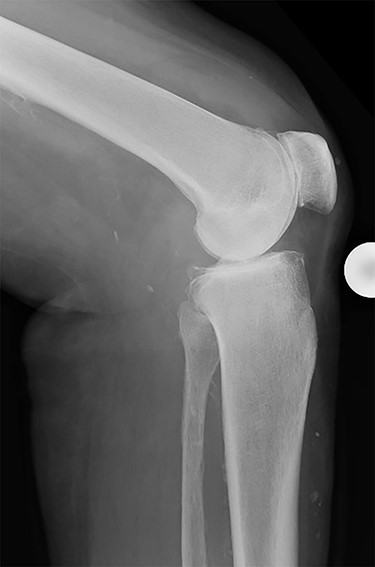

Conventional radiographs in an anteroposterior and lateral view showed advanced osteoarthritis (Kellgren stage III) accentuated medially and patellofemoral (Figs 1 and 2). An additional magnetic resonance imaging (MRI) was performed, which confirmed the medial accentuated osteoarthritis, it revealed some minor meniscal tears, some signs of general synovitis and joint effusion (Figs 3 and 4).